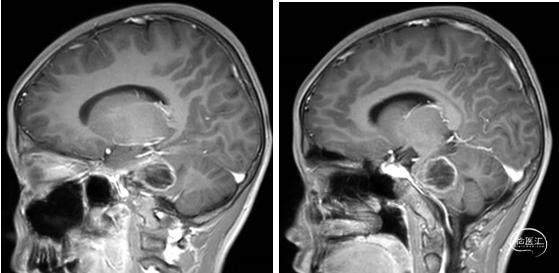

术前MRI

术后MRI